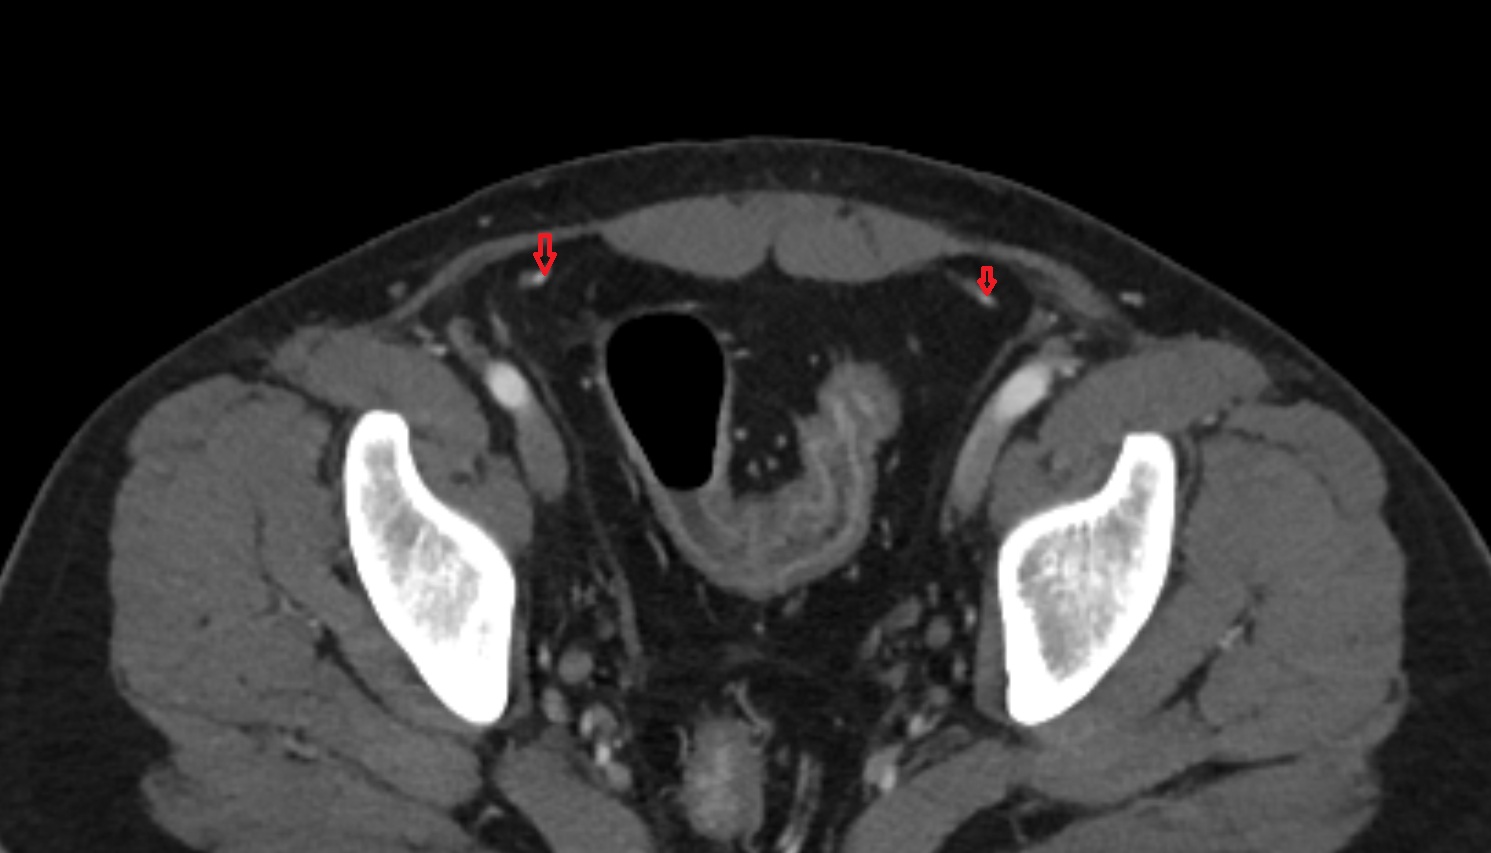

- Round ligament of uterus